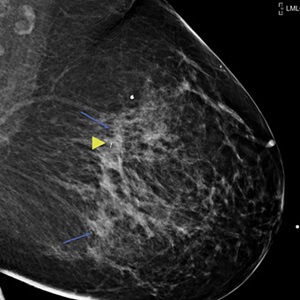

At MDACC, this participation is facilitated using 3D-printed models of breast MRIs.

“Showing the location of a tumor on an anatomically correct 3D breast model instead of an MRI on a screen makes it easier for the patient to understand their options and make informed decisions,” Dr. Santiago said.

When used during the consultation, 3D printed models can increase a patient’s understanding of anatomy and the goal of the proposed surgical treatment.

“Personalized 3D breast models influence various elements in the decision-making process, including a patient’s understanding of treatment options, benefits, risks and side effects, while also integrating their personal values and addressing any uncertainties,” Dr. Santiago said.